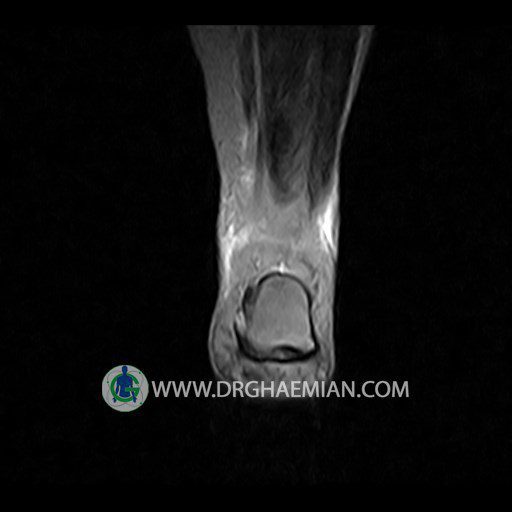

پزشکان اغلب از تصویربرداری ام آر آی برای تشخیص و درمان عارضه های پزشکی که فقط با استفاده از اشعه ایکس یا میدان مغناطیسی و امواج رادیویی قابل مشاهده است، استفاده می کنند. دستگاه ام آر آی تصاویر دقیق از ساختار های داخلی بدن ایجاد می کند. در این کیس تورم مچ پا بیمار مشاهده می شود.

گزارش پزشک :

LEFT KNEE MRI

(Without contrast)

Technique: Sagittal T1, T2 , Axial GE , coronal & sagital fatsat .